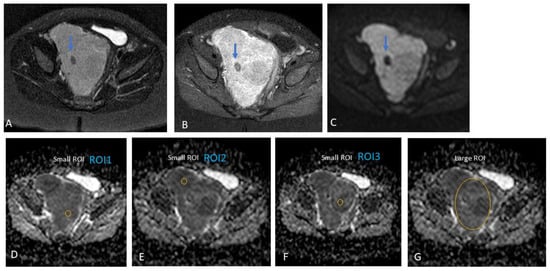

2.3.2. MRI Interpretation